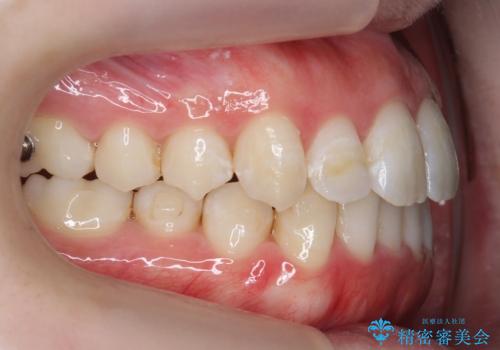

下の歯のがたつき 上より気になる

- 前歯のがたつきが気になって来院。

下の歯のがたつきが上よりも多い状態でした。

前歯のがたつきもしっかり治り、喜んでいただけました。